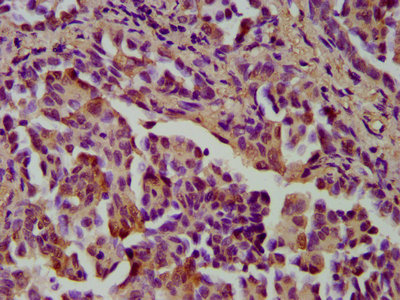

Immunohistochemistry of paraffin-embedded human colon cancer using CSB-PA00224A0Rb at dilution of 1:100

IHC image of CSB-PA00224A0Rb diluted at 1:400 and staining in paraffin-embedded human lung cancer performed on a Leica BondTM system. After dewaxing and hydration, antigen retrieval was mediated by high pressure in a citrate buffer (pH 6.0). Section was blocked with 10% normal goat serum 30min at RT. Then primary antibody (1% BSA) was incubated at 4°C overnight. The primary is detected by a biotinylated secondary antibody and visualized using an HRP conjugated SP system.